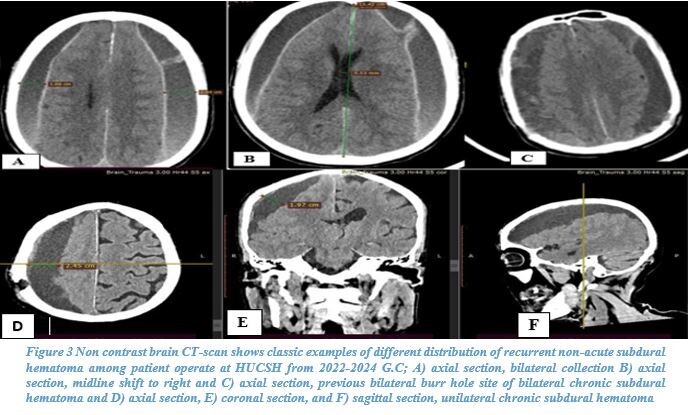

CT scan was the primary imaging modality used (87.6%). An iso-dense subdural hematoma was the most common radiological finding (54.7%), followed by a hypo-dense hematoma (42.9%). Most hematomas were unilateral (71.4%) with a left-sided predominance (41%). Most hematomas measured more than 2 cm in thickness (70.2%), and 59% demonstrated a midline shift of 5–10 mm (see Figures 2–4).

Radiologically, iso-dense hematomas were most common (54.7%), followed by hypo-dense hematomas (42.9%), with the majority showing a significant midline shift and thickness greater than 2 cm. These findings suggest delayed presentation, a common issue in low-resource settings, which result in larger hematoma volumes. The reliance on CT scans (87.6%) as the primary diagnostic tool is consistent with practices in most African neurosurgical centers due to limited MRI availability and prolonged scan times.8,9,13,22,23